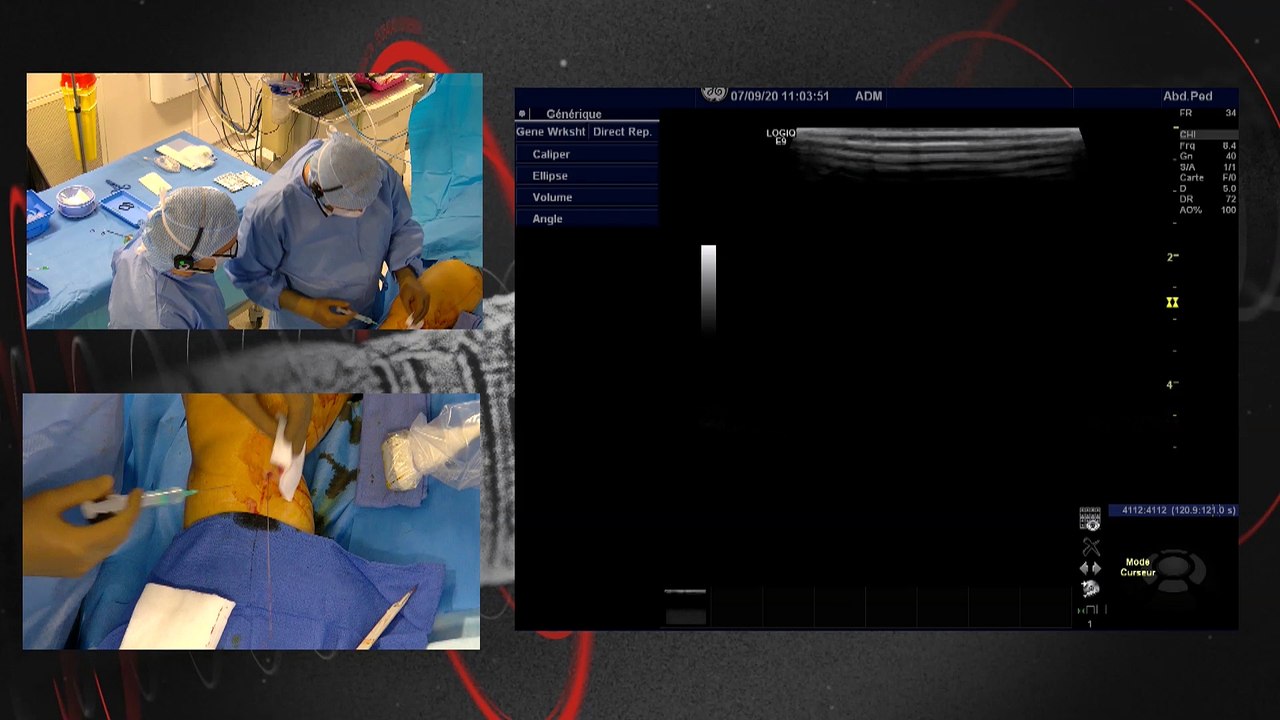

18:35 Case 1: Versatility of Directional Atherectomy in a multilevel calcified lesion: the role of combined therapy

Case 2: Effective use of specialty balloon (Chocolate) followed by DCB in an SFA occlusion